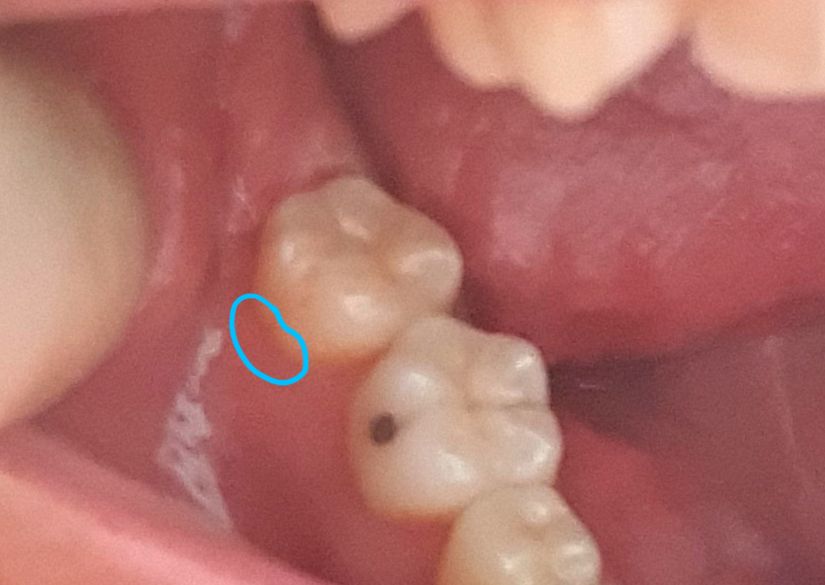

사랑니 발치 후 바로 앞 어금니 잇몸 내려감?

안녕하세요. 작년 5월 매복 사랑니 발치(좌측) 후 문제가 없다가

최근 시려와서 보니, 우측 어금니에 비해 잇몸이 많이 내려왔더라고요.

사진/그림과 같이 앞 어금니 잇몸 부분이 시린데...

• 1번 째 사진